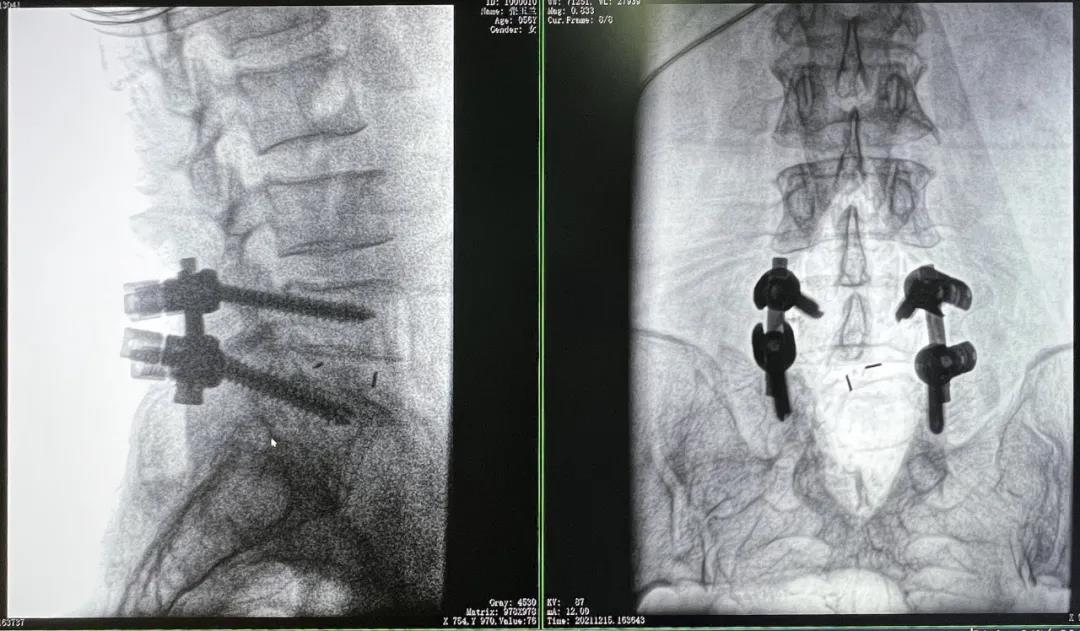

患者1:女性,56歲,L5/S1椎間盤椎板減壓+釘棒固定術

患者下腰部疼痛,活動受限,伴有左下肢疼痛5年,久站或彎腰干活時疼痛加劇,臥床休息后疼痛癥狀緩解,近一個月情況加重,需行椎板減壓+釘棒固定術。

3D C形臂擺位及手術前二維影像

醫生在影像引導下在L5/S1椎弓根處打入醫用螺釘